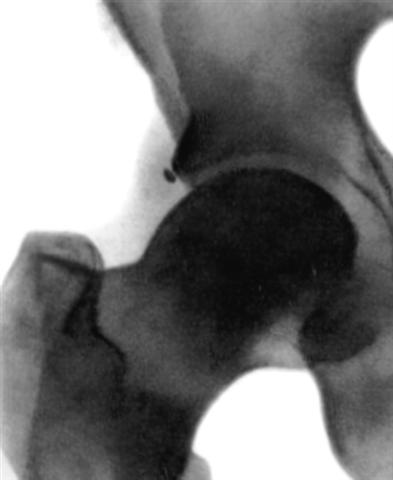

Рис. 6а). Рентгенограмма тазобедренного сустава (прямая проекция) взрослого в норме.